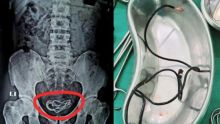

Ingin Mengukur Panjang Penisnya, Remaja ini Masukkan Kabel USB ke Alat Kelamin Hingga Tersangkut Internasional - 19 Sep 2021, 19:52

Bosan Selama Pandemi, Pria Ini Masukkan Alat Kelamin ke Gembok dan Tak Bisa Lepas, Dokter Lakukan Operasi Agar Tak Membusuk Internasional - 14 Aug 2021, 09:41